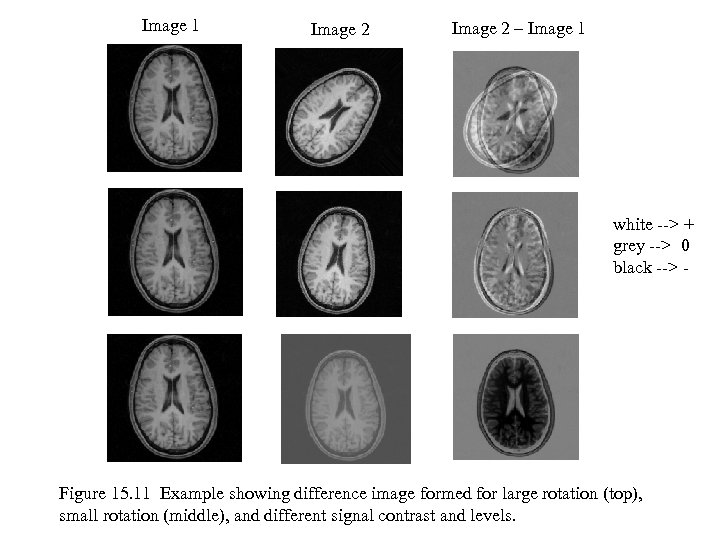

Image 1 Image 2 – Image 1 white --> + grey --> 0 black --> - Figure 15. 11 Example showing difference image formed for large rotation (top), small rotation (middle), and different signal contrast and levels.